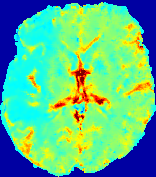

LesionRefer to captionRefer to captionRefer to captionRefer to captionRefer to captionRefer to caption𝐕rgbsubscript𝐕𝑟𝑔𝑏{\bf{V}}_{rgb}Refer to captionRefer to captionRefer to captionRefer to captionRefer to captionRefer to caption𝐕2subscriptnorm𝐕2{\|\bf{V}}\|_{2}Refer to captionRefer to captionRefer to captionRefer to captionRefer to captionRefer to captionRefer to caption3.53.53.52.82.82.82.12.12.11.41.41.40.70.70.70.00.00.0(mm/s)𝑚𝑚𝑠(mm/s)D𝐷DRefer to captionRefer to captionRefer to captionRefer to captionRefer to captionRefer to captionRefer to caption0.0200.0200.0200.0160.0160.0160.0120.0120.0120.0080.0080.0080.0040.0040.0040.0000.0000.000(mm2/s)𝑚superscript𝑚2𝑠(mm^{2}/s)Slice #1Slice #2Slice #3Slice #4Slice #5Slice #6

Figure 3: PIANO feature maps for one stroke patient, where the lesion is located in the left hemisphere. Top row: segmented stroke lesion region (white) on different slices, obtained from ISLES 2017. The corresponding slices for the PIANO feature maps are shown in the following rows.

For a better insight into an estimated velocity field 𝐕𝐕{\bf{V}} and diffusion field 𝐃𝐃{\bf{D}}, we compute the following maps: (1) 𝐕rgbsubscript𝐕𝑟𝑔𝑏{\bf{V}}_{rgb}: Color-coded orientation map of 𝐕=(Vx,Vy,Vz)T𝐕superscriptsuperscript𝑉𝑥superscript𝑉𝑦superscript𝑉𝑧𝑇{\bf{V}}=(V^{x},V^{y},V^{z})^{T}, obtained by normalizing 𝐕𝐕{\bf{V}} to unit length and mapping its 3 components to red, green, blue respectively; (2) 𝐕2subscriptnorm𝐕2\|{\bf{V}}\|_{2}: 222 norm of 𝐕𝐕{\bf{V}}; (3) D𝐷D: scalar field in Eq. 5.

Fig. 3 and Fig. 4 show the PIANO feature maps estimated from two ISLES 2017 patients: all are highly consistent with the lesion in both cases. Details of the blood flow trajectories are revealed in 𝐕rgbsubscript𝐕𝑟𝑔𝑏{\bf{V}}_{rgb} by the ridged patterns and the sharp changes of colors in the unaffected (right) hemisphere, while the flat patterns appearing within the lesion provide little directional information about the velocity and indicate low velocity magnitudes. Velocity magnitudes are more directly visualized via 𝐕2subscriptnorm𝐕2\|{\bf{V}}\|_{2}, from which one can easily locate the lesion where 𝐕2subscriptnorm𝐕2\|{\bf{V}}\|_{2} is low. D𝐷D also indicates lower diffusion values in the lesion, though with less contrast potentially due to the fact that it captures the accumulated effect of CA diffusion at the voxel-level.